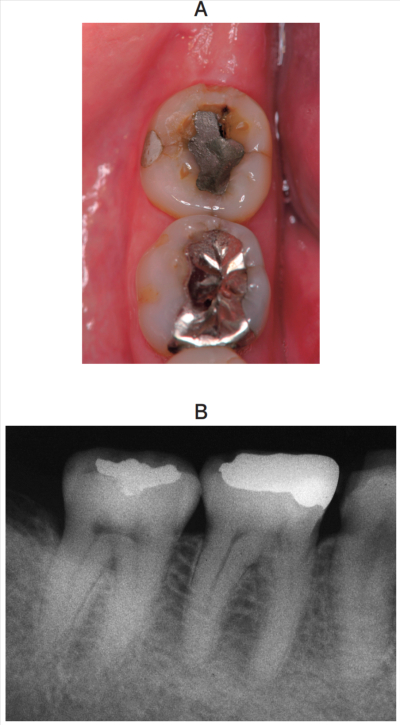

60歳の女性。下顎右側第二大臼歯の冷水痛を主訴として来院した。40年前に齲蝕治療のため直接修復を受け、特に異常はなかったが、1年前から気になっているという。咬合面の修復物を除去し、コンポジットレジン修復を行うこととした。初診時の口腔内写真とエックス線写真を別に示す。

修復物の除去で正しいのはどれか。すべて選べ。